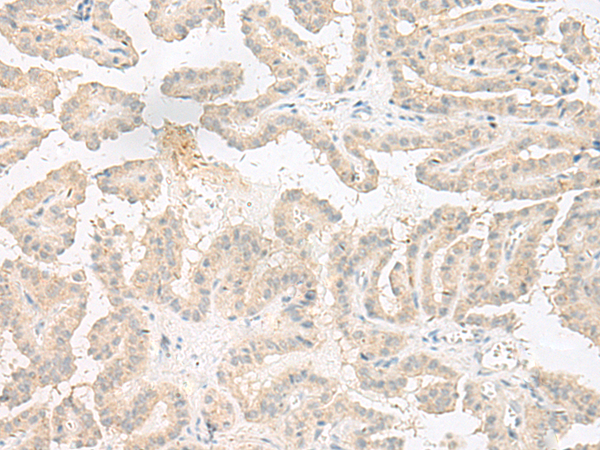

分类: 科研抗体货号: P06577别名: PIF79; GMEB-2; P79PIF应用: IHC反应种属: Human, Mouse, Rat